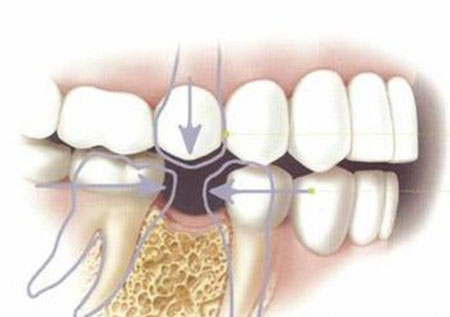

3、对“邻牙”健康有害缺牙空隙两侧的牙,由于失去支撑,也向空隙处倾斜,发生牙齿排列紊乱,必然形成较大的缝隙、移位、扭转,造成食物嵌塞等。

4、长期缺牙,可导致相对的牙齿伸长,为以后修复造成不便,同时伸长的牙齿与相邻牙齿之间亦容易嵌塞。 》》》相关阅读:在廊坊,种植牙能用多长时间?

5、长期缺牙可致局部牙槽骨因缺少咀嚼力量的刺激而萎缩,给后期的修复造成困难,同时也影响修复的效果。可见长时间缺牙不修复的危害是不容忽视,牙齿缺失后,应及时到口腔医院进行全面的检查,医师会根据患者的口腔情况,综合判断,制定相应的修复方案。同时为了你的健康,必须注意牙齿的保健,多吃含钙丰富的食物,做好口腔的卫生保健,定期进行口腔检查。